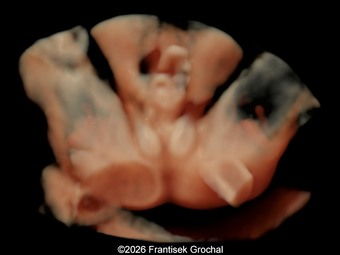

A 34-year-old woman, G2P1001, presented to our maternal fetal medicine unit at 30 weeks of gestation for a late fetal anatomic survey. The fetus was female with low-risk noninvasive prenatal testing. The following findings were observed.